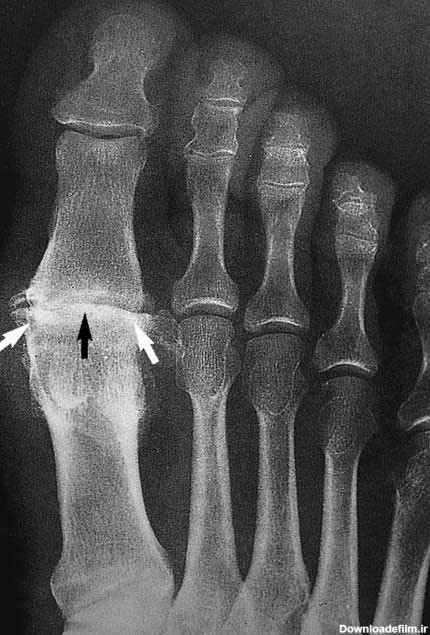

رادیوگرافی ها ممکن است با اشعه مرکزی عمود بر صفحه IR یا زاویه دهی 10 درجه به سمت خلف ( به سمت پاشنه ) بدست آید . زمانی که زاویه ی 10 درجه به سمت خلف استفاده می شود ، اشعه مرکزی عمود بر متاتارس ها و کوتاه شدگی کاهش می یابد .همچنین فضای مفصل TMT در ناحیه ی میانی کف پا بهتر نشان داده می شوند . ( تصاویر 6-39,6-40)